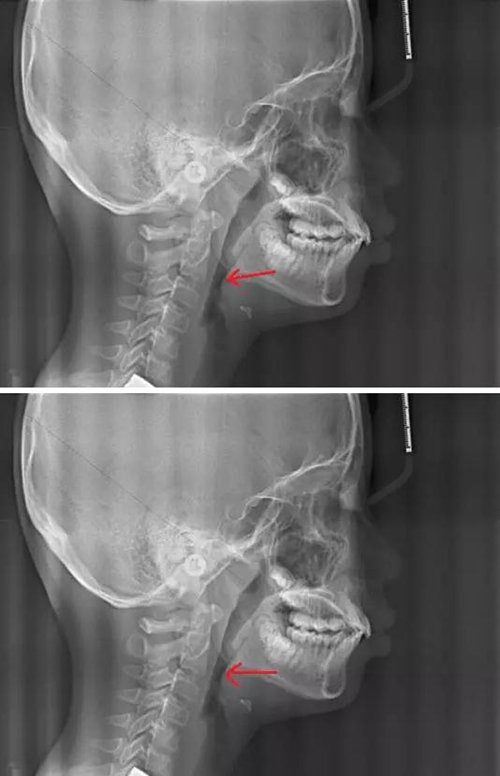

最后我們來對比一下正常的腺樣體和扁桃體的形態(tài)及位置,我們可以看到,正常的腺樣體和扁桃體在同一個位置形態(tài)的差異。

3.jpg